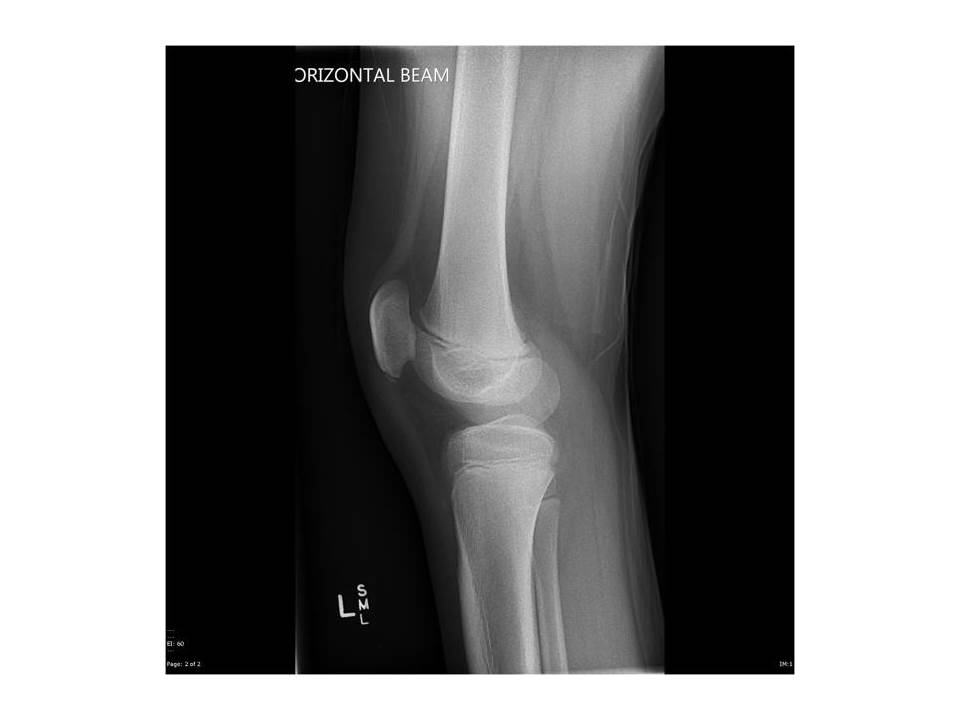

На фото  - рентгенограма колінного суглоба (бічна проекція).

Це рентгенограма дорослої людини чи дитини?

Обгрунтуйте свою відповідь. Для цього використайте знання з теми 10 Розділу ІІІ.